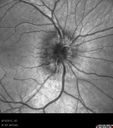

Papilledema - Spectral Domain OCT used for Diagnosis - 14 year old Child - IR Photo1048 views14-year-old was with optic nerve swelling asymptomatic - picked up during routine eye exam. OD 20/20, OS 20/32

SD-OCT is used to differentiate optic disc edema from optic nerve head drusen (which are not yet calcified in children).